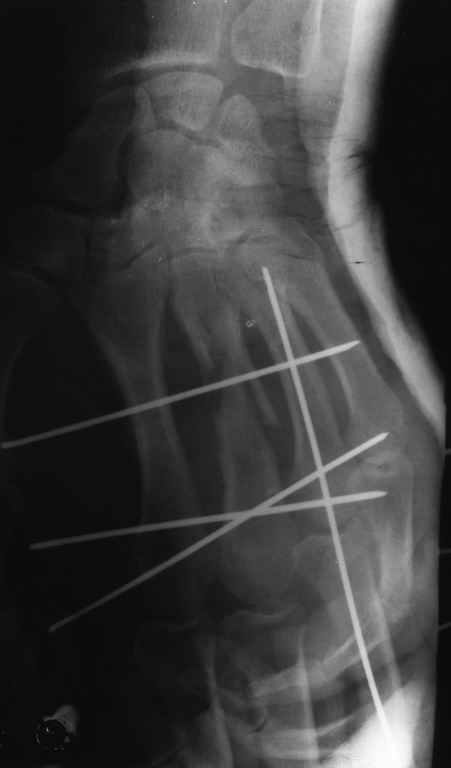

Диагноз на 15.07.05: Стойкая смешанная дермотеногенная контрактура 3,4 пальца правой кисти 3 степени.

-- удалить спицы;

-- сделать рентгенограмму;

Диагноз: Стойкая Смешанная дермотеногенная контрактура 3,4 пальца правой кисти.

Судя по выписному эпикризу, рентгенограммам и фотографиям, пациенту

показано этапное лечение.

К сожалению, мне непонятна локализация кадра

(прилагаю).

Это 3 или 4 межпальцевой промежуток? Гранулирующая рана или свищ?

Зачем спица в 4 Пястной кости?